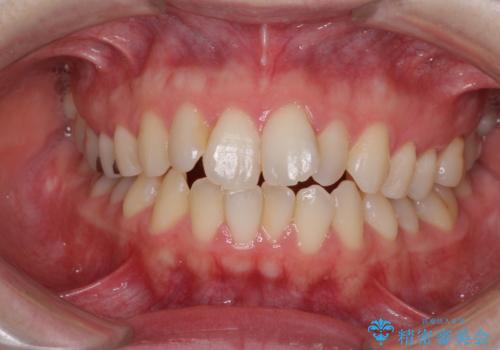

- 前歯のデコボコを気にして来院された患者様です。

下顎が骨格的にずれており、上下正中を合わせることは難しいことが予想されたため、デコボコの解消を主目的として、ワイヤー矯正を行うこととしました。